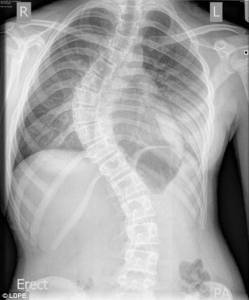

xray Share this: Share on X (Opens in new window) X Share on Facebook (Opens in new window) Facebook Like Loading...